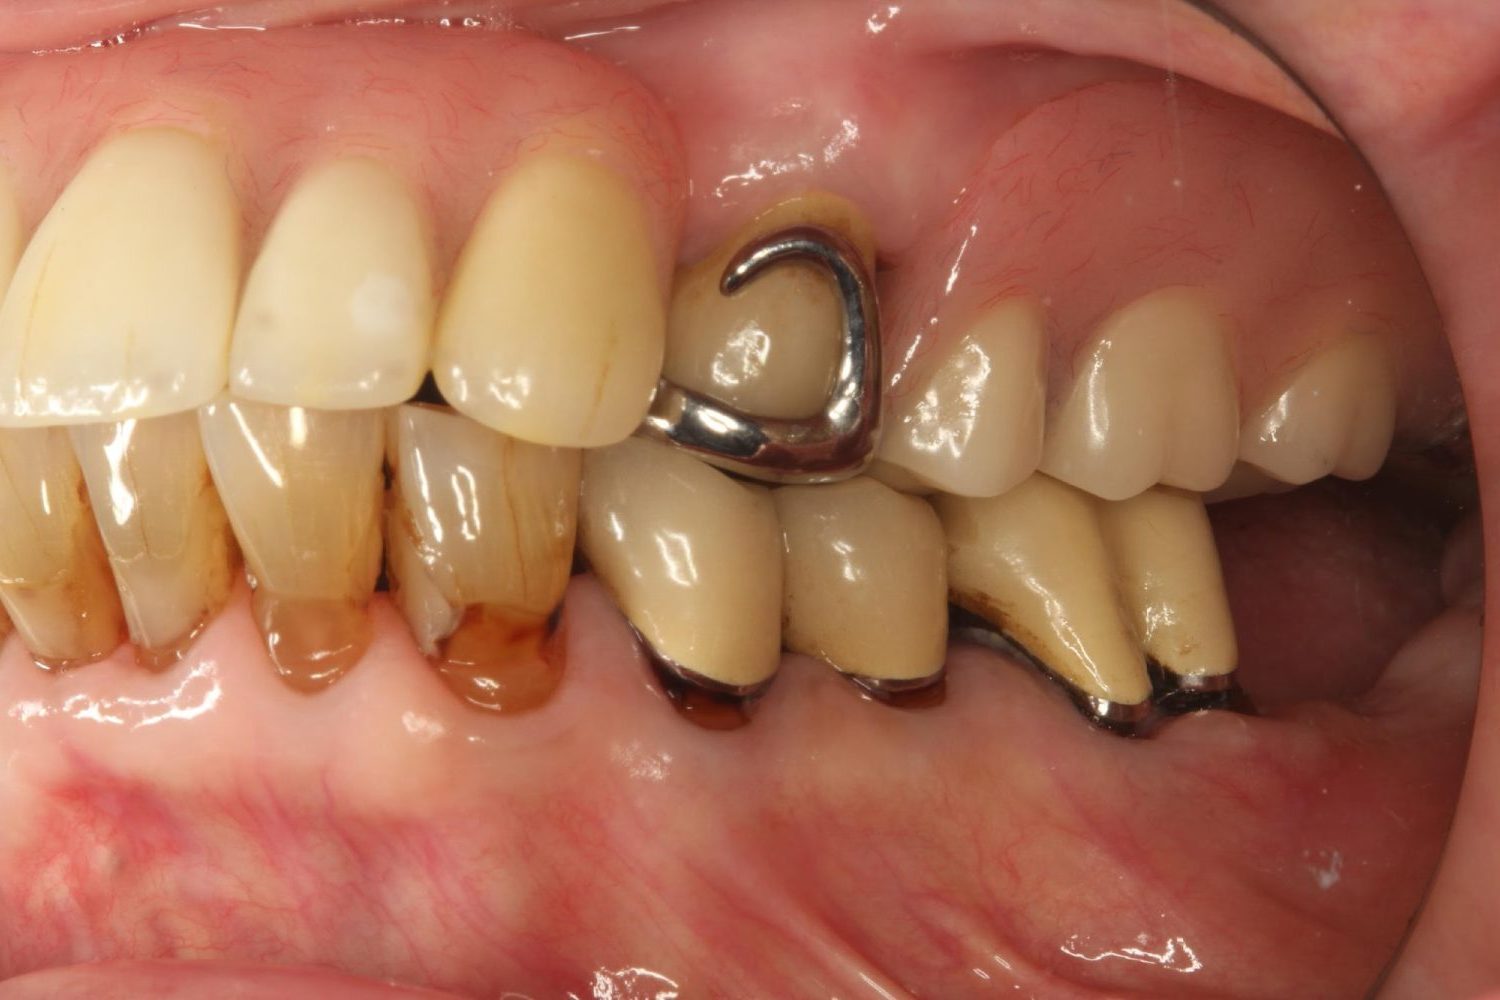

インプラント治療の症例紹介④

Before

After

主訴

義歯による疼痛

治療内容

下顎舌側に骨隆起があり義歯困難な状態。保存不可能な歯の抜歯を行い、インプラントを埋入し咬合再構成を行った。

歯の欠損の対合歯の挺出等を修正し咬合平面を揃え咬合再構成を行った症例。